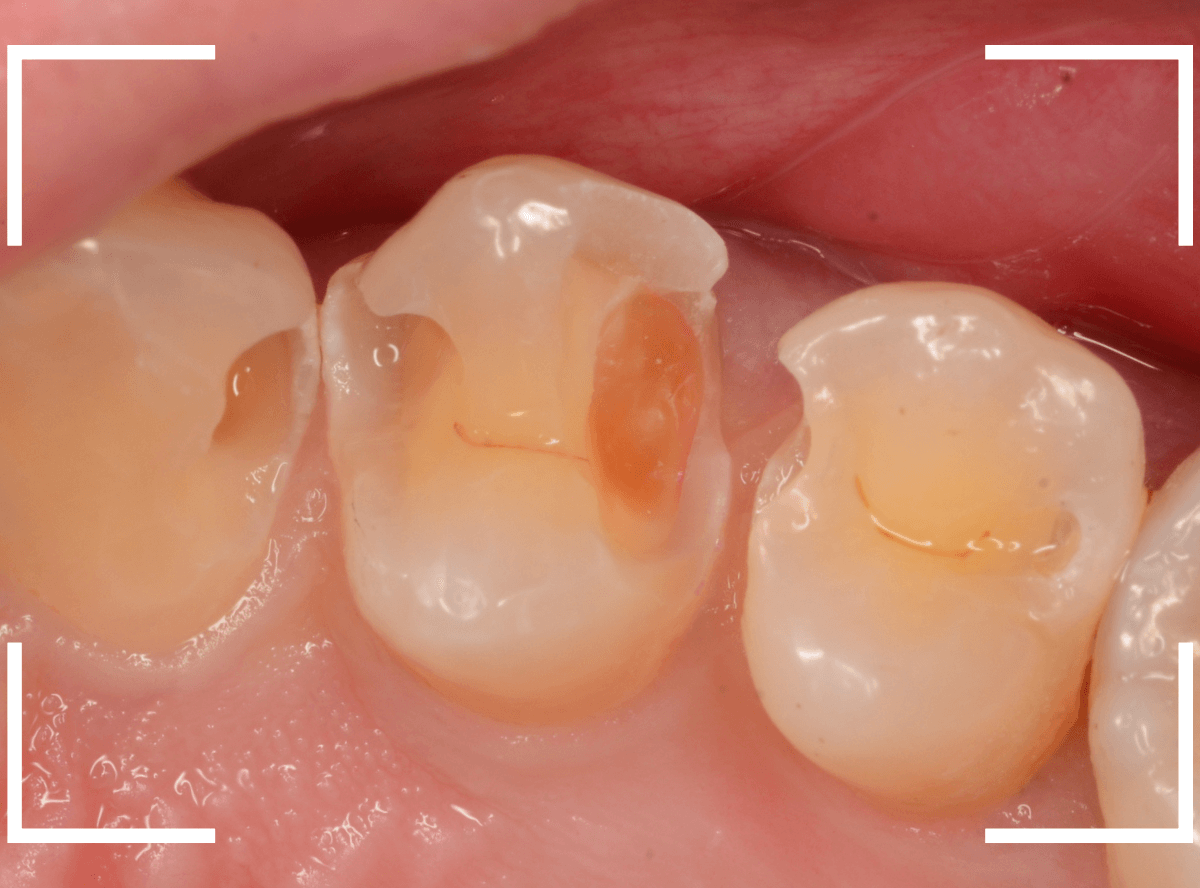

Case.21 神経に達しそうな2本の大きな虫歯

上の小臼歯の側面が明らかに虫歯になっている患者さんです。

患者さんは特に症状を感じてなさそうですが、恐らくは中で大きな虫歯になっているでしょう。

このように、自覚症状からだけでは虫歯の状況は診できません。

レントゲン写真で確認します。

青い線が歯の神経、赤い線が虫歯と思われる部分です。

2本とも、神経に達してしまいそうな大きな虫歯であると思われます。

まず、奥の歯のつめものを外してから、虫歯の治療を開始します。

手前の歯が大きな虫歯が見えてきました。

神経に達してしまいそうな虫歯ですので、ある程度削ったところで、少しずつエキスカという道具で掻き出すようにして、虫歯を除去します。

虫歯は歯を溶かして進行しますので、骨よりも固い歯もちょっと掻き出すとボロボロと崩れるようになってしまっています。

かなり虫歯を除去したところで、手前の歯は神経が顔を出してしまいました(露髄といいます)。

神経を除去する治療が必要かもしれないです。

全ての虫歯を除去したところです。

幸い、後ろの歯は薄皮一枚のところで神経まで達していない虫歯ですんでいましたが、大きな虫歯だった事には変わりありません。

いつものように、神経が痛み出さないように祈りつつ、お薬で保護して経過観察します。

虫歯は症状からだけでは判断できませんが、定期受診によって、このような大きな虫歯の処置は避けられる事がほとんどです。

かならず歯科の定期受診をしてくださいね。